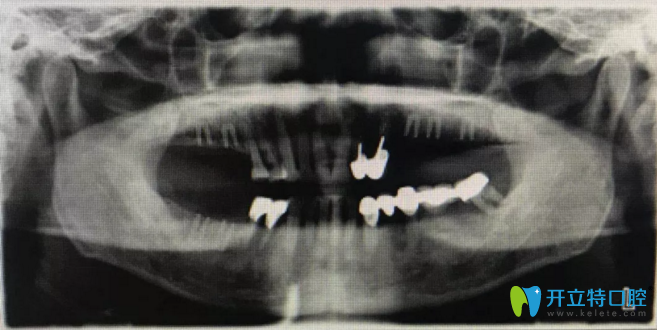

術(shù)前擬植入位點(diǎn)設(shè)計(jì)